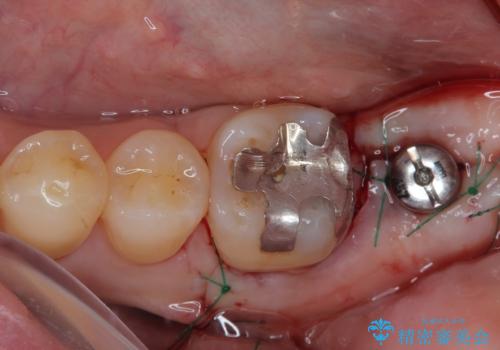

左下の奥歯は状態が非常に悪く、保存は困難と判断されたため、インプラントによる補綴治療が必要でした。

上顎左右の歯をアンカースクリューを用いた部分矯正により位置を修正し、オールセラミッククラウンにて補綴治療を行うこととしました。

矯正治療に時間はかかりましたが、外側に飛び出した歯が内側に収まったことで、非常に歯が磨きやすくなったとのことでした。